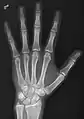

• Hand - DP and Oblique

• Fingers - DP and Lateral

• Thumb - AP and Lateral